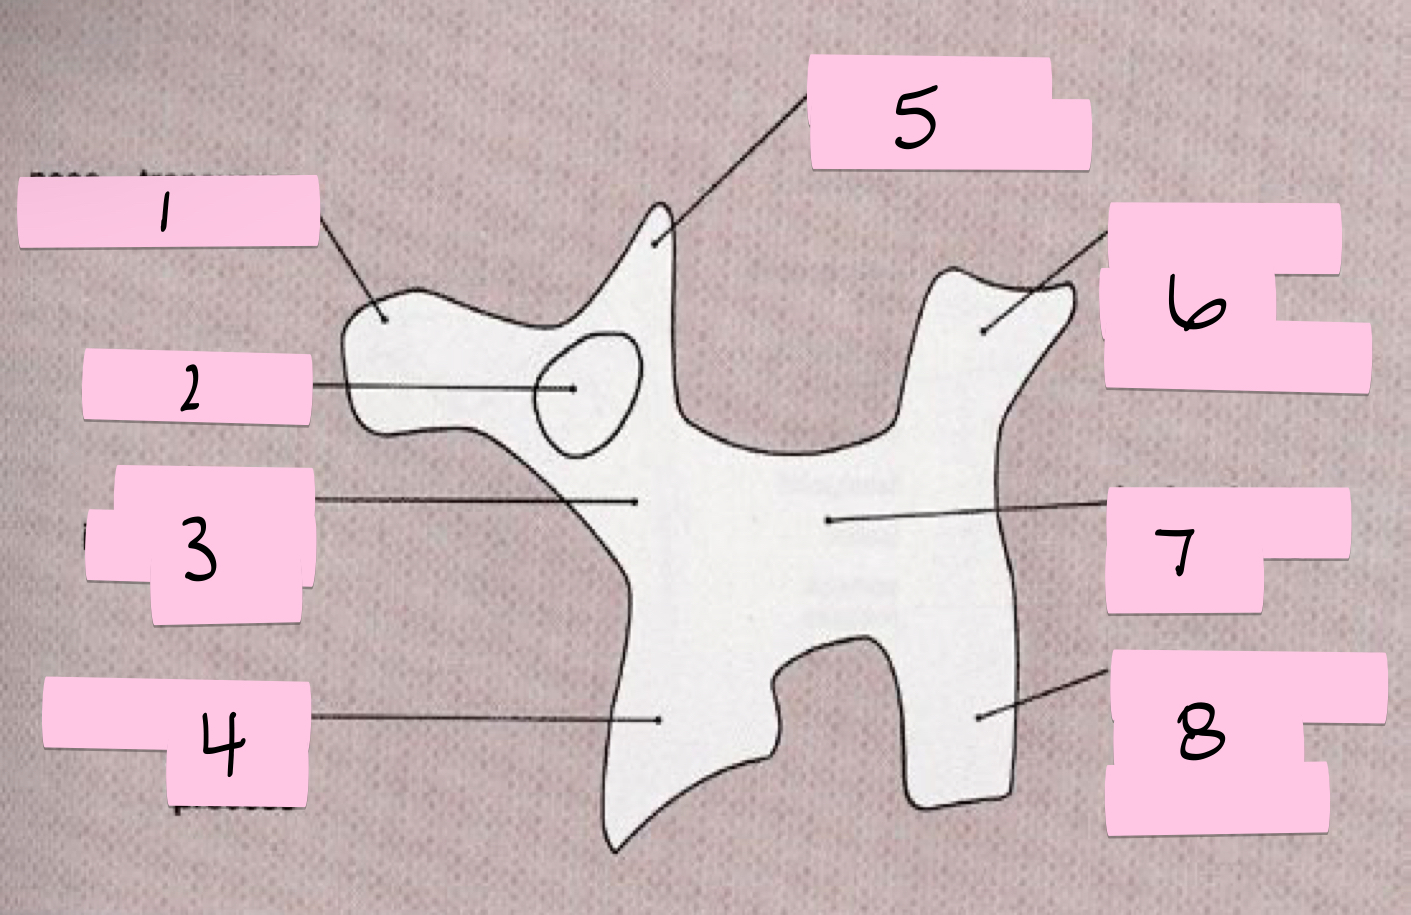

What is 1 pointing to?

Nose- Transverse process

What is 2 pointing to?

Eye- Pedicle

What is 3 pointing to?

Neck- Pars interacticularis (isthmus)

What is 4 pointing to?

Foreleg- Inferior articular process

What is 5 pointing to?

Ear- Superior articular process

What is 6 pointing to?

Tail- Superior articular process of opposite side

What is 7 pointing to?

Body- Lamina and spinous process

What is 8 pointing to?

Hindleg- Inferior articular process of opposite side